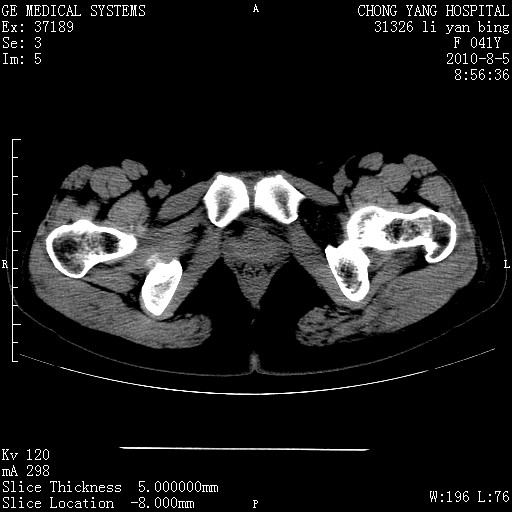

标题: CT28214:F41Y 血尿二十天,建议盆腔平扫加增强。 [打印本页]

标题: CT28214:F41Y 血尿二十天,建议盆腔平扫加增强。